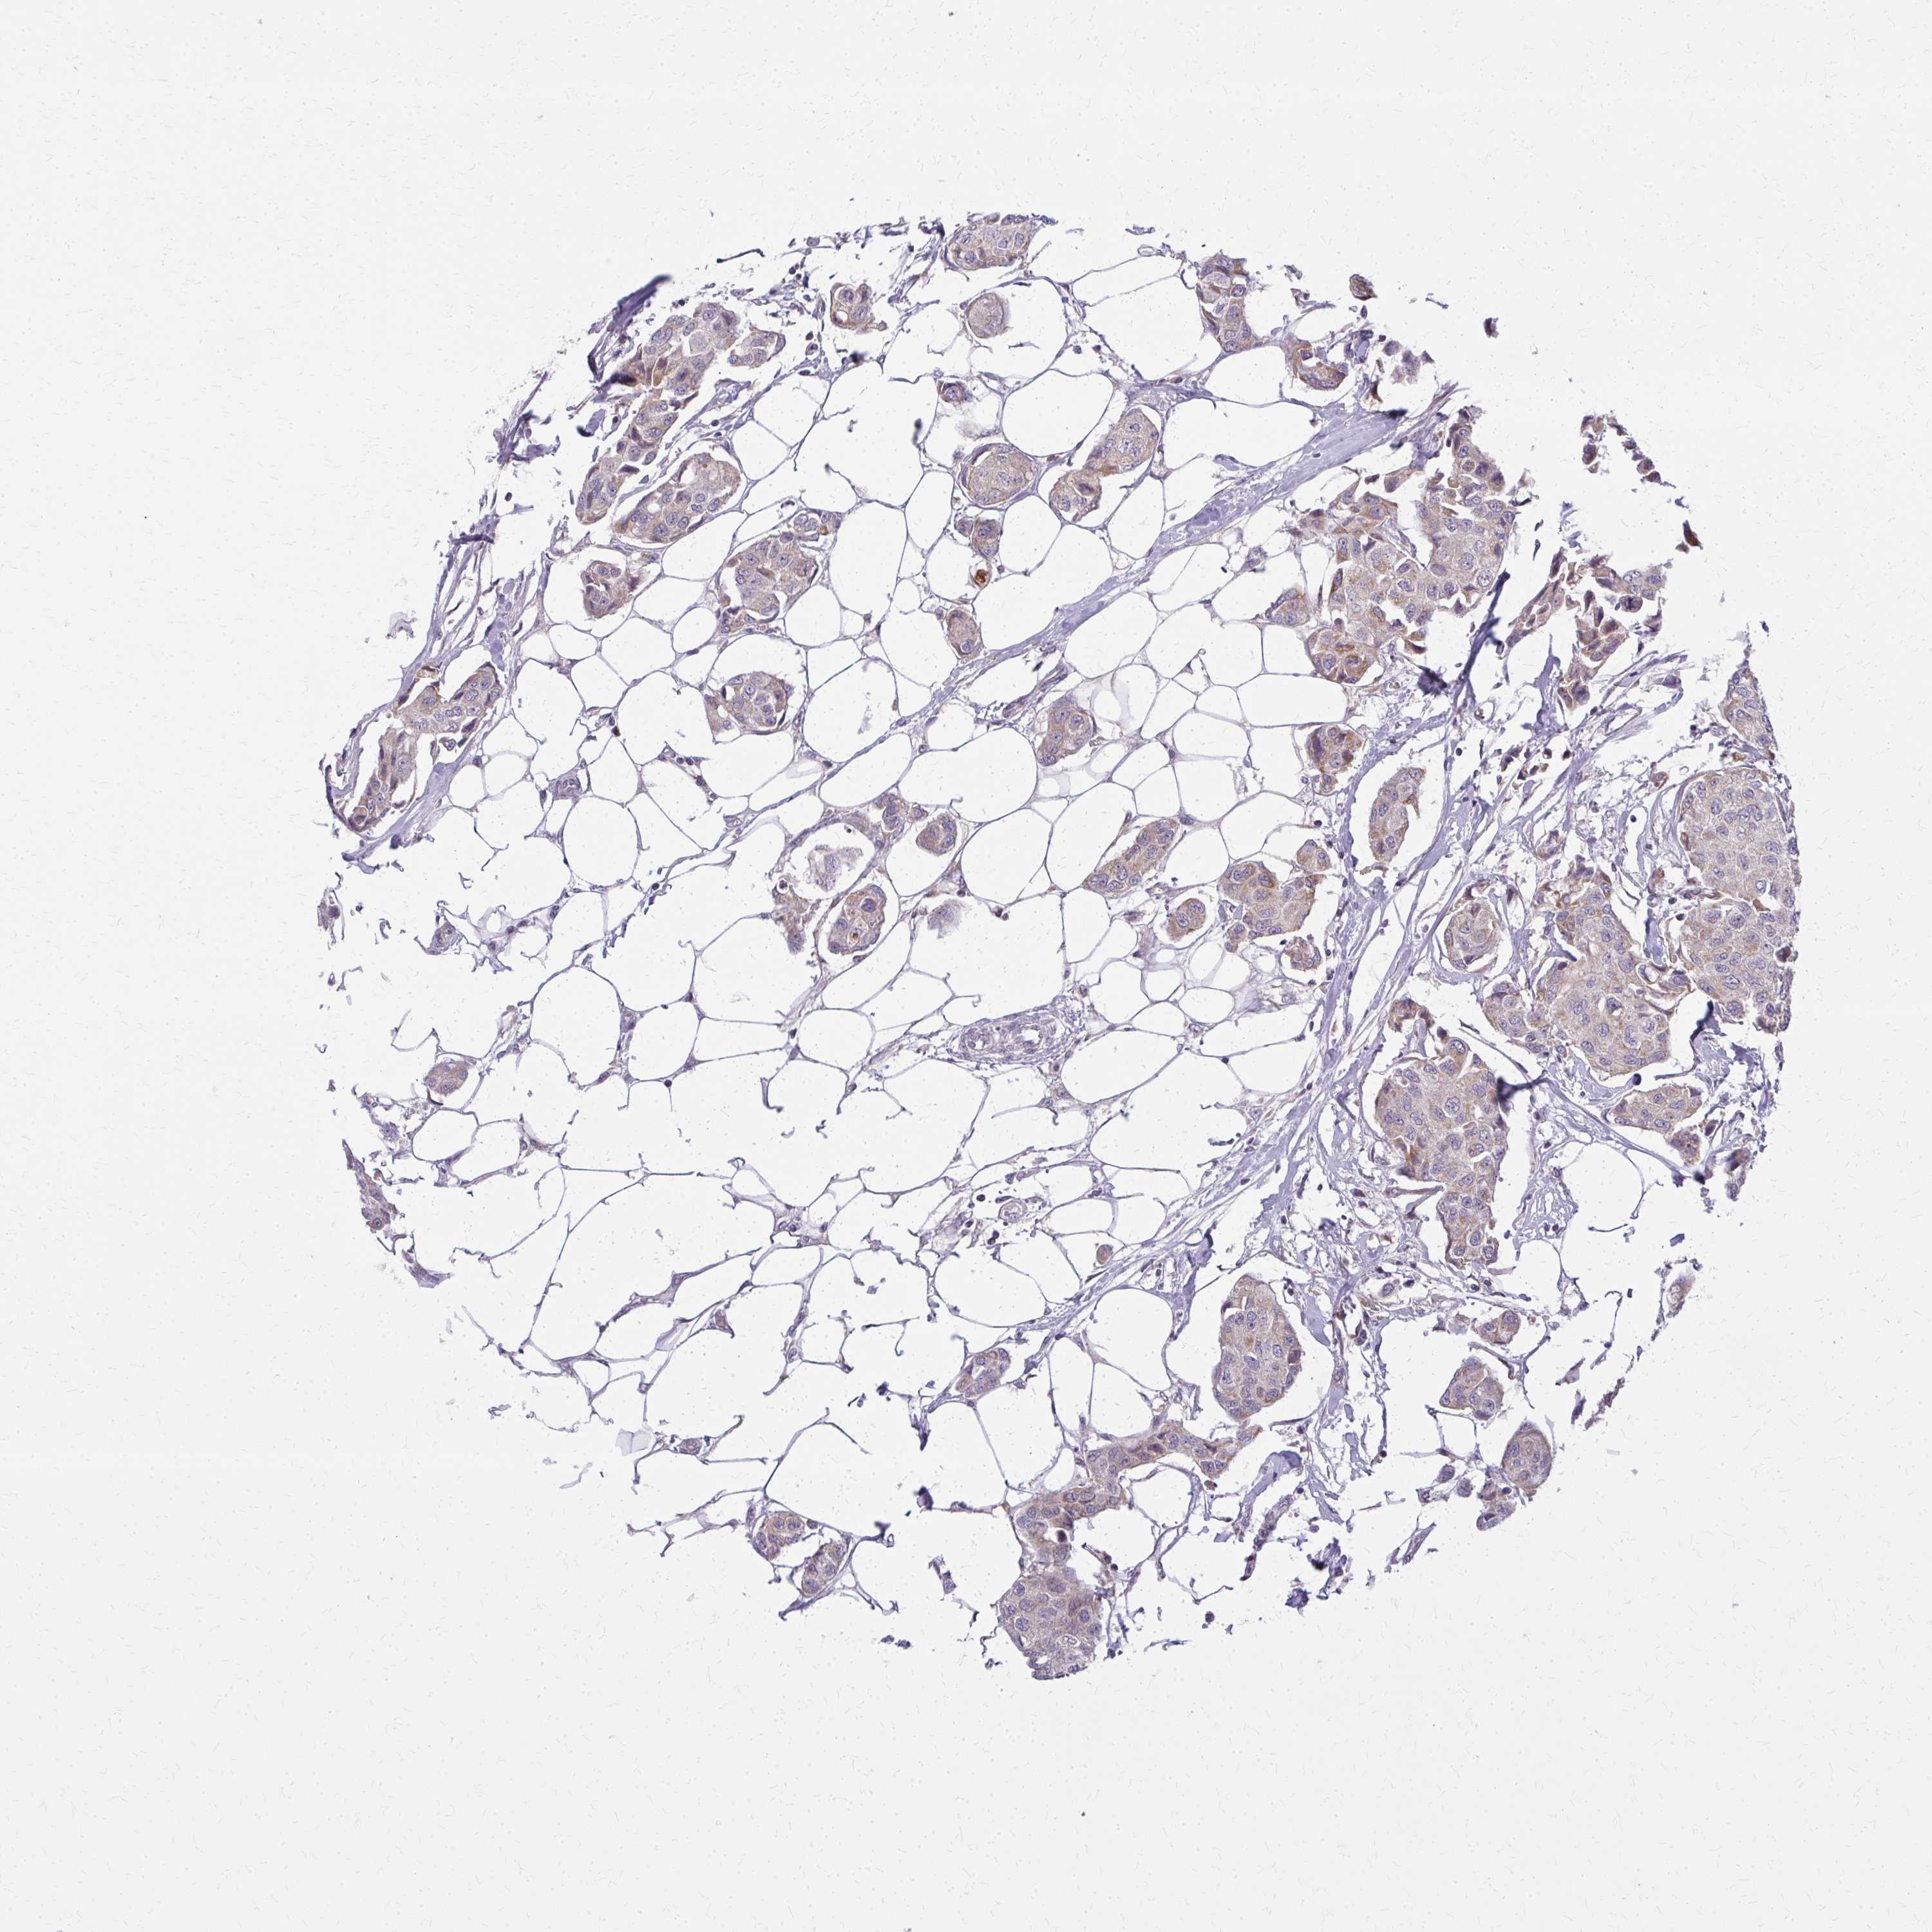

CANCER BREAST CANCER Show tissue menu

BRCA TCGA BRCA VALIDATION PROTEIN EXPRESSION